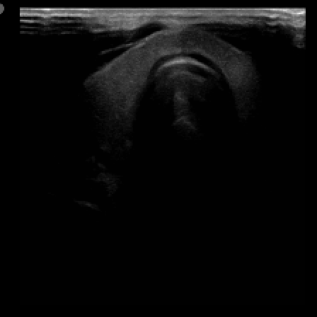

We propose a novel approach that adapts hierarchical vision foundation models for real-time ultrasound image segmentation. Existing ultrasound segmentation methods often struggle with adaptability to new tasks, relying on costly manual annotations, while real-time approaches generally fail to match state-of-the-art performance. To overcome these limitations, we introduce an adaptive framework that leverages the vision foundation model Hiera to extract multi-scale features, interleaved with DINOv2 representations to enhance visual expressiveness. These enriched features are then decoded to produce precise and robust segmentation. We conduct extensive evaluations on six public datasets and one in-house dataset, covering both cardiac and thyroid ultrasound segmentation. Experiments show that our approach outperforms state-of-the-art methods across multiple datasets and excels with limited supervision, surpassing nnUNet by over 20\% on average in the 1\% and 10\% data settings. Our method achieves $\sim$77 FPS inference speed with TensorRT on a single GPU, enabling real-time clinical applications.